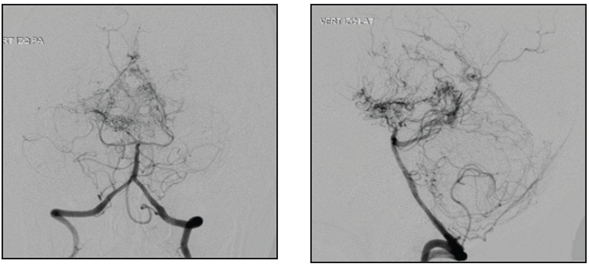

A 45-year-old female, ethnically mestizo patient with no significant past medical history was admitted to the emergency room of a quaternary hospital in the city of Cartagena (Bolívar) on July 1, 2019, due to a one week history of moderately intense holocranial headaches and a subsequent generalized tonic-clonic seizure, with sphincter relaxation and an unspecified length of the seizure. On admission to the emergency room, her blood pressure was 140/90 and the rest of her vital signs were normal with no focal neurological deficits. A simple computerized tomography (CT) of the head showed intraparenchymal hemorrhage in the right basal ganglia, mild multifocal small vessel ischemic disease, malacic changes in the right occipital region and an old left frontal ischemic event adjacent to the left lateral ventricle (Figure 1). The initial lab exams showed no abnormalities, with normal red and white blood cell and platelet counts, and nitrogen compounds, electrolytes and coagulation times all within normal limits. Cerebral panangiography found thinning of the internal carotid and posterior cerebral arteries (the latter seen in 50% of cases) with abnormal neovascularization in the basal nuclei, compatible with moyamoya disease (Figure 2). With these results, her possible treatment plan was assessed by a neurosurgery medical panel, concluding that she could benefit from endovascular treatment. However, in light of the high risk of recurrent bleeding, this procedure was postponed for at least four weeks.

Various tests for assessing cerebral vasculature, such as angiotomography and angioresonance, are used for diagnosis, with good results. However, cerebral panangiography (also known as digital subtraction angiography) is the gold standard for definitive diagnosis of moyamoya disease, when the characteristic arteriographic appearance is seen. It detects stenosis of the terminal portion of the internal carotid artery and its proximal branches, as well as the formation of the network of collaterals 4. In our case, cerebral panangiography was ordered as part of the workup for intracraneal hemorrhage in a young patient, and it showed progressive thinning of both internal carotid arteries, along with neovascularization and bilateral disappearance of the medial and anterior cerebral arteries.